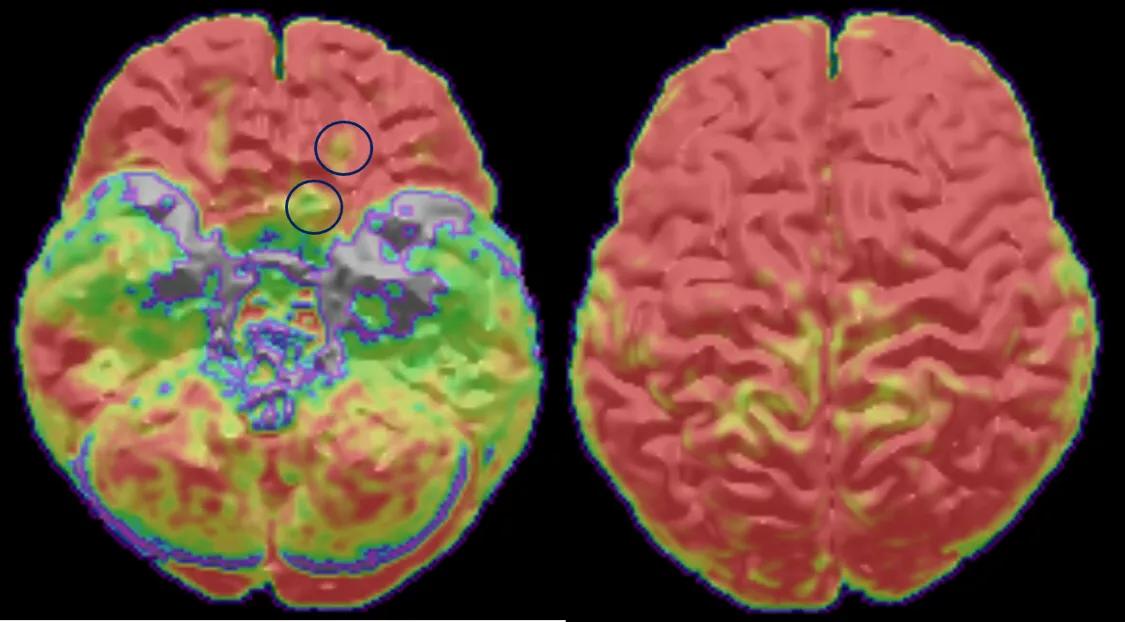

其次,最近癫痫病学一个重要的进展就是影像学的发展。多序列、高场强、高分辨率MRI(更高级的磁共振)广泛应用于癫痫术前评估中,也就是说硬件更强了。而且,各种影像后处理方法如PET-MRI融合技术、基于体素及皮层表面的形态学分析(VBM,SBM)开始应用于临床,提高了病灶的检出率,也就是软件更强了。这部分工作大多都是癫痫中心医生自己来做的。所以癫痫中心的医生往往会和患者要磁共振的光盘,那是要看原始文件,进行影像后处理。